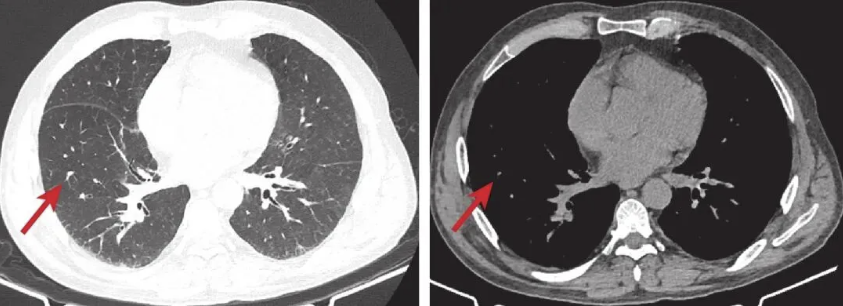

④ 转归:切换至APRV+PPV后,氧合持续显著改善(表3),第7天成功撤机,序贯HFNC(SpO2维持95%左右)。循环稳定,停用血管活性药物,炎症指标显著下降(白细胞计数 6.2×109/L,降钙素原0.2 ng/mL),复查胸部CT(第7天,图2):双肺弥漫性实变影较前显著吸收,仅残留少量磨玻璃影。第9天转出ICU,第23天痊愈出院。出院1月随访肺功能基本恢复(图3)。

图2 入院第7天复查胸部CT检查图像

与图1相比,双肺弥漫性实变影显著吸收,仅残留少量磨玻璃影(箭头所示)。